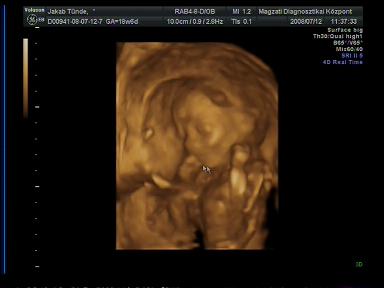

Jók a pocifotók!

Szeretnék segítséget kérni fizetős genetikai UH ügyben: ki hol járt és mennyire volt megelégedve a szolgáltatással? Ja, és a legfontosabb, hányadik hétig lehet menni ilyen genetikai UH-ra???

Ugyanis ma voltam a kórházban UH-n és kb. 3 perc alatt lerendeztek. A doki közlékeny volt, de nagyon rohamtempóban történt minden. Szóval hogy megnyugodjak teljesen, szeretnék elmenni egy alaposabb vizsgálatra is. A nemének beazonosításában is nagyon készséges volt doki bácsi, de Pötty szégyenlős volt (lehet, ez már utal valamire

) és jól összezárta a lábait. Amúgy az ő vizsgálatuk szerint minden ok. És medence végű, ami nem tudom, hogy jót jelent-e, mindenesetre a doki ezzel magyarázta, hogy nem tud sokat mocorogni, mert nincs túl sok helye ott.